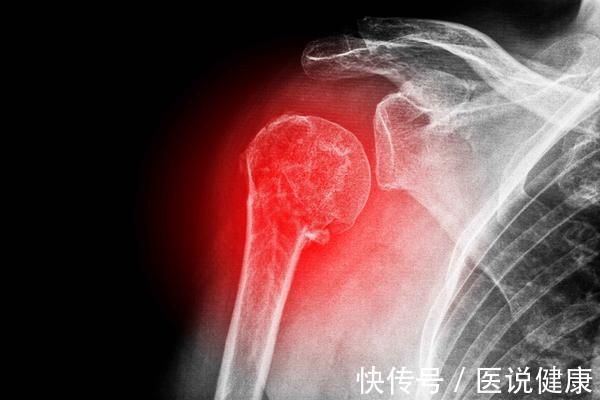

4、骨骼强健

中医认为,肾主骨,也就是说骨头的健康与否和肾脏息息相关,只有肾脏足够好,骨骼才会表现出强健的状态,反之则容易有骨质疏松,牙齿松动以及腰酸背痛等症状。